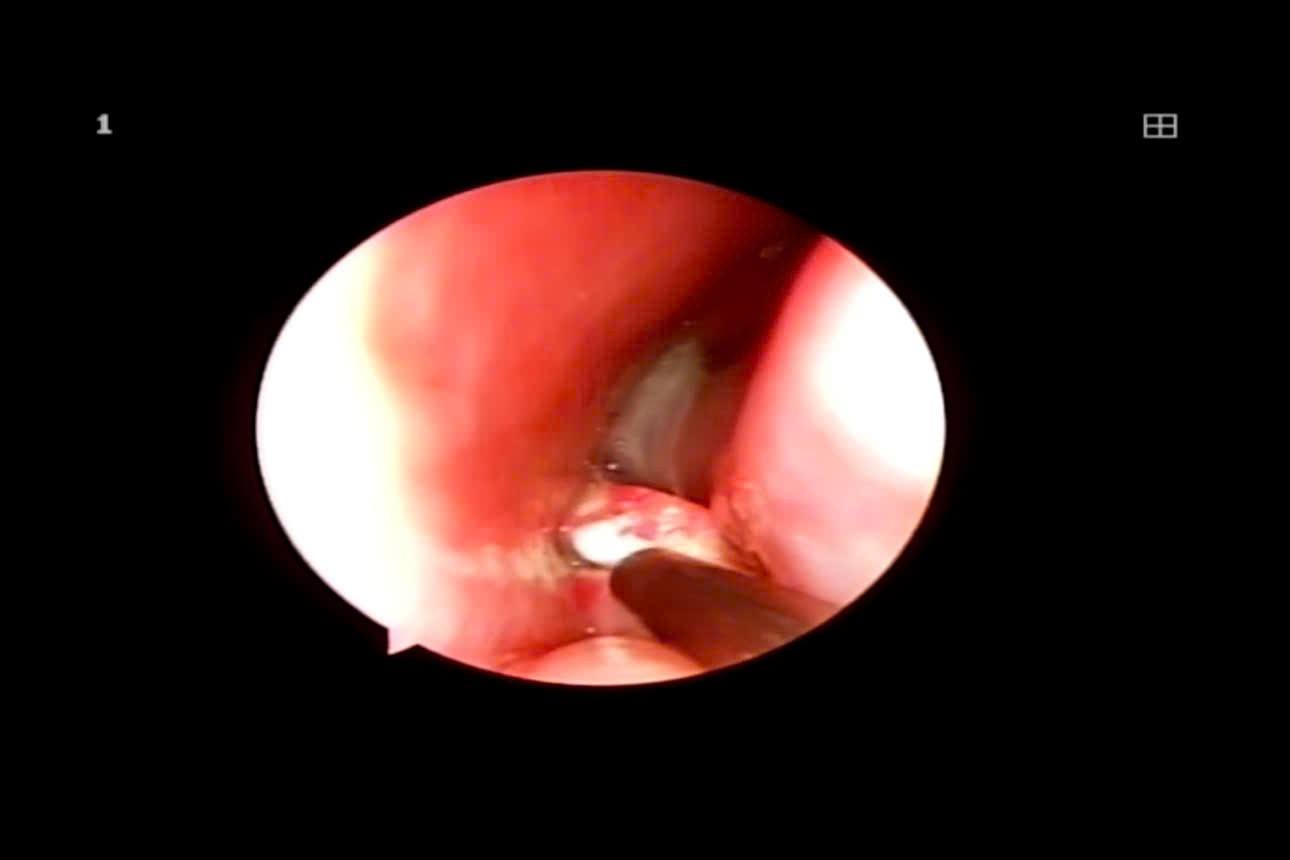

ThS.BSCKII Trịnh Thị Vân - người trực tiếp thăm khám cho bệnh nhi chia sẻ, khi đến khám trong hốc mũi trái của trẻ có rất nhiều dịch mủ, trẻ đau, quấy khóc nhiều. Phải đến khi mũi trẻ đc làm sạch, bác sĩ soi lại mới phát hiện sợi dây chun nằm sâu trong hốc mũi gây viêm nặng cho các tổ chức xung quanh. Trước đó, cháu bé đã được gia đình đưa đi khám tại nhiều cơ sở y tế với chẩn đoán ban đầu là viêm VA và được kê đơn điều trị nội khoa. Tuy nhiên, sau mỗi đợt điều trị, triệu chứng chỉ thuyên giảm rất nhẹ rồi lại tái phát khiến gia đình hết sức lo lắng. Tình trạng càng trở nên nghiêm trọng hơn khi cháu bé bắt đầu sưng hạch ở góc hàm hai bên.

Dị vật được phát hiện trong mũi em bé 3 tuổi

Ngay khi phát hiện dị vật trong mũi bệnh nhi, Bác sĩ khoa Tai Mũi Họng Bệnh viện Bưu điện đã tiến hành gây tê và nội soi lấy dị vật ra ngoài. Thủ thuật được thực hiện nhanh chóng, an toàn. Theo Bác sĩ Vân, trẻ sẽ được theo dõi, điều trị tại Bệnh viện khoảng 5 ngày theo phác đồ chuyên môn nhằm làm sạch hoàn toàn vùng niêm mạc bị viêm. Sau khi tình trạng viêm nhiễm ổn định trẻ sẽ được nạo VA nhằm hạn chế tái phát tình trạng viêm mũi xoang.